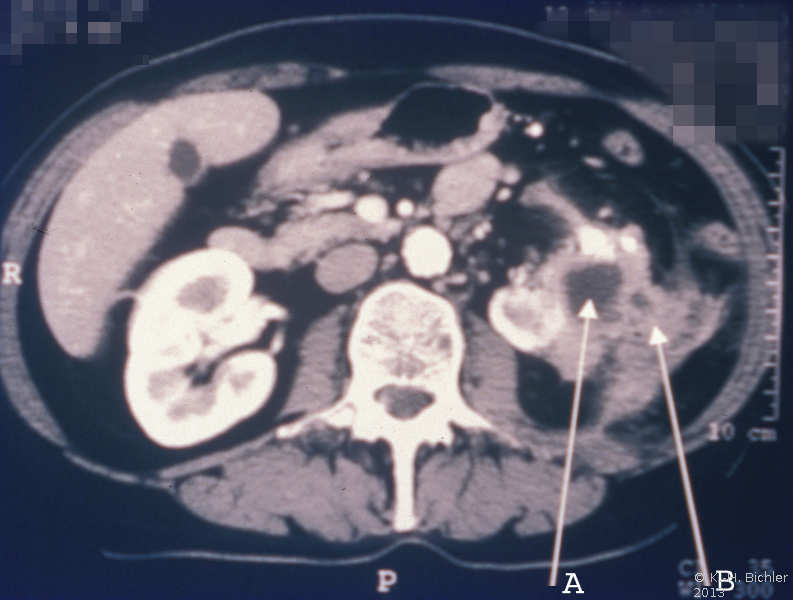

Papillennekrose

Sie tritt zumeist bei Patienten mit Diabetes Mellitus bzw. bei Harnwegsobstruktionen auf (Komplizierte Pyelonephritis). Dabei können eine oder alle Papillen befallen sein. Histologisch findet sich eine koagolative Infarktnekrose, d.h. die Umrisse von befallenen Tubuli sind erhalten. Leukozytäre Reaktionen finden sich an den Rändern der Nekrosebezirke Literatur:Robbins: "Pathologic Basis of Disease", Saunders Philadelphia, 1999.